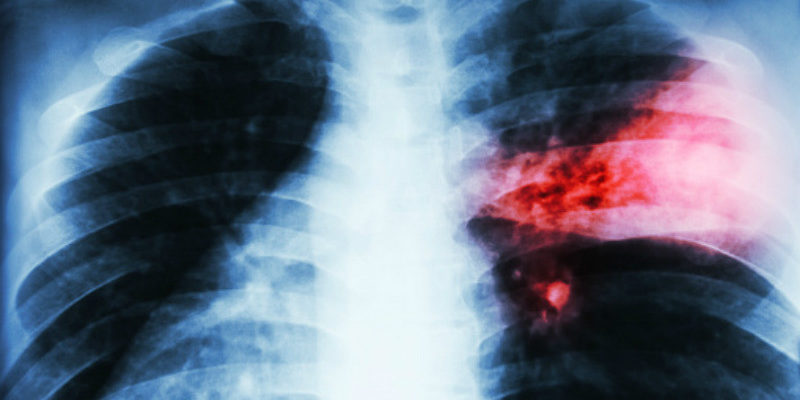

У большинства детей заболевание возникает на фоне острого респираторного вирусного заболевания. При не эффективном лечении раннее развитие очаговых инфильтратов начинает появляться уже через семь суток с ухудшением общего состояния, лихорадочным периодом и нарушением в деятельности некоторых систем. Очень рано на рентгенологических снимках обнаруживаются легочные инфильтраты, в скором времени ко всему присоединяется раздражение плевральной оболочки. Клиническая симптоматика острого воспаления доли легкого проявляется синдромом гнойного очага и недостаточности дыхания. Для этого типа характерно бурное развитие заболевания, появляется гипертермия, отличающаяся стабильностью, одышка, изменение кожных покровов в виде ценотического оттенка. В более запущенных и тяжелых состояния возникают признаки шокового состояния.

При объективном обследовании обнаруживается неподвижность грудной клетки на участке поражения. Легочная форма деструктивного процесса характеризуется появлением гнойных очагов на базальной поверхности легких. Клинически проявляется признаками интенсивной интоксикации изменением кожных покровов и респираторными нарушениями. Пораженный участок настолько напряженный, что даже через стенку можно обнаружить скопление гнойного содержимого. Абсцесс, образованный в легочной ткани может быть гигантских размеров и располагаться в боковых отделах, этот процесс, уплотняясь, смещает здоровые органы средостения в противоположную сторону. Гигантские абсцессы протекают относительно доброкачественно без развития сепсиса. Буллезная форма легочной деструкции — это тонкостенные воздушные образования, которые опасности особой не представляют.